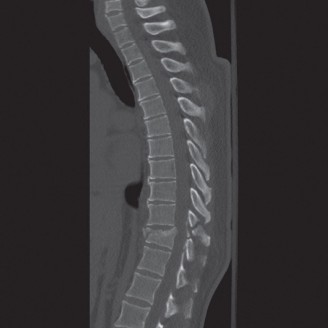

The correct answer is (A). As the case scenario strongly suggests an injury to the spine at the thoracolumbar junction, a CT scan of both the thoracic and lumbar regions is indicated. An MRI should not be the first imaging study obtained. Standing films should not be obtained in a trauma patient with a potentially unstable spine injury. A CT myelogram would only be obtained if an MRI was indicated but the patient had a contraindication to an MRI. Images of the above patient are shown inFigures 1–25 and 1–26. This injury is best characterized as which of the following? 1. Compression fracture

Figure 1–25

Figure 1–26

Discussion

The correct answer is (B). The images demonstrate an L1 vertebral body fracture with a small degree of kyphosis. There is comminution of the vertebral body with a posterior vertebral body fragment that is slightly retropulsed into the spinal canal. This separate posterior vertebral body fragment (which is noncontiguous with the pedicles) is the hallmark of a burst fracture. Compression fractures do not have any posterior vertebral body involvement. A Chance fracture, also known as a seat belt fracture or flexion–distraction injury, will exhibit distraction of the posterior elements through bone, bone-ligament, or purely ligament structures, with an axis of rotation somewhere within the anterior vertebral body or anterior to the vertebral body. A fracture dislocation exhibits translational deformities between the injured levels. While there appears to be a translational deformity on the sagittal CT, the vertebral bodies of the uninjured levels above and below are actually well aligned.